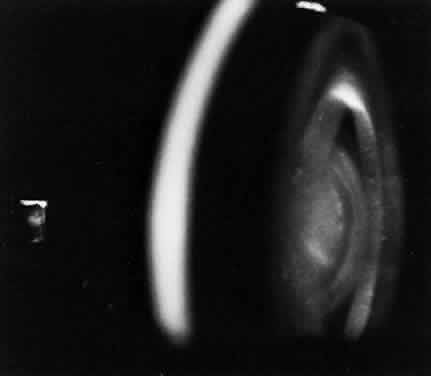

The lens in homocystinuria is much more mobile than in the Marfan syndrome. This may be related to the clinical observation of progressive irregularity of the zonular fibers and the appearance of a fringe of white zonular remnants at the equator of the lens and on the surface of the ciliary body (Fig. 1).12,13 Henkind and Ashton first reported histopathologically the ocular findings in four eyes of three homocystinuric patients. They found the zonular fibers to be deficient adjacent to the lens. These zonules had recoiled to the surface of the ciliary body and were matted and retracted into a feltwork that fused with a greatly thickened basement membrane of the nonpigmented epithelium. The greatly thickened basement membrane overlying the ciliary body in homocystinuria has subsequently been shown by electron microscopy to be composed of degenerate zonular material.14 In addition, Ramsey and coworkers noted that the degree of zonular abnormality was related to age: the younger the patient, the more normal-appearing zonular fragments composed of oriented filaments that could be identified.14 The zonular fibers are composed of glycoproteins with a high concentration of cysteine, which may explain their susceptibility to abnormal function in homocystinuria.15,16

Fig. 1. Inferior dislocation of the lens in a homocystinuric patient. Note the absence of most zonular fibers. (Nelson LB, Maumenee IH: Ectopia lentis. Surv Ophthalmol 27:143, 1982)